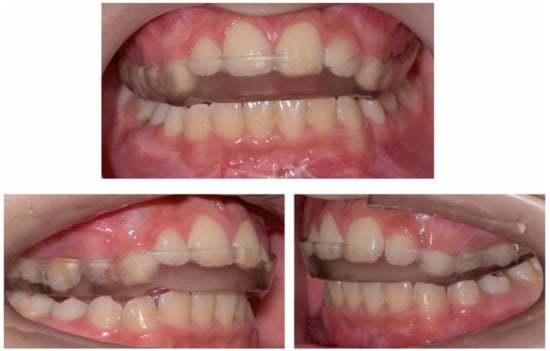

2.2.1. Initial Examination